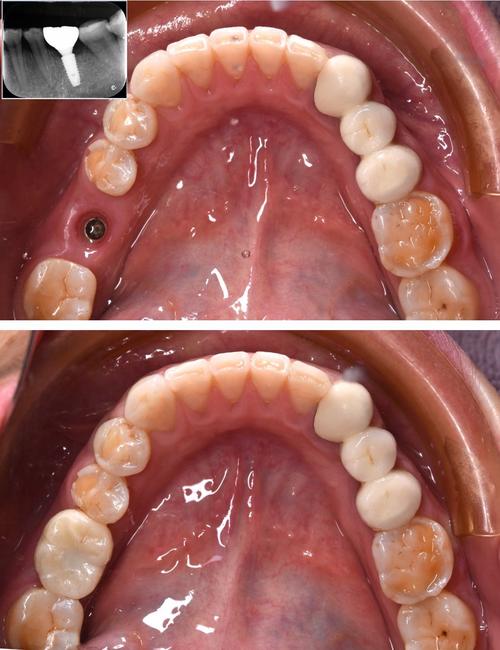

(图片来源网络,侵删)- 在严格无菌的手术室进行。

(图片来源网络,侵删)- 牙龈形态稳定后,医生会取模(或使用口内扫描仪获取数字化数据)。